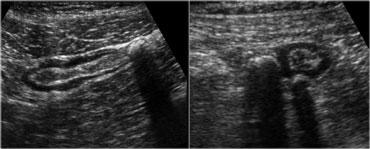

Siêu âm thời gian thực cho phép quan sát tác động của lực ép. So sánh hồi tràng bình thường đang co (trái) với hồi tràng giãn, xẹp ở cùng bệnh nhân vài giây sau (phải)

- Đặc điểm sau đặc biệt hữu ích để đánh giá xem các cơ quan hoặc mô có mềm mại hay cứng chắc hay không.

Siêu âm thời gian thực cho phép quan sát tác động của lực ép.

Ở ngoài cùng bên trái là hồi tràng bình thường đang co và bên cạnh là hồi tràng giãn, xẹp vài giây sau đó.